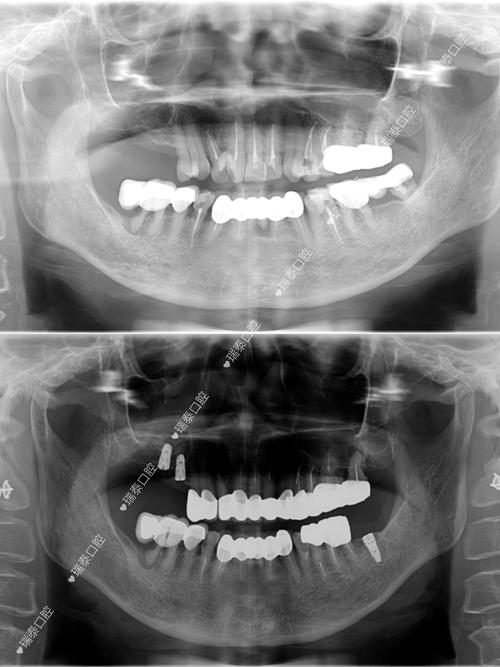

- 伪影: 虽然钛种植体本身不会产生大量伪影,但它仍然会在MRI图像上产生一定程度的伪影(图像变形或信号缺失),尤其是在种植体周围,伪影的大小和范围取决于种植体的尺寸、形状、位置以及MRI的场强和序列,这可能会影响对种植体周围骨组织或邻近结构的清晰观察,但通常不会导致检查无法进行。